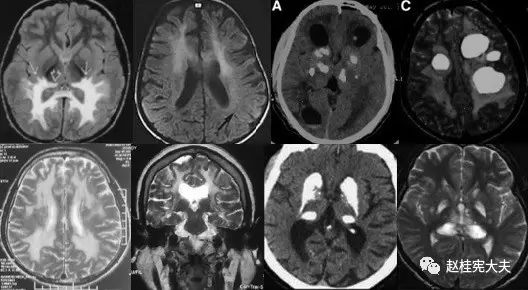

重要申明:以下每个部分会配磁共振图片,因疾病和影像之间存在同病异象、同像异病,为避免误导,图片不标注疾病,请各自鉴赏,另其中有部分图片来源于网络,有疑问可与本人联系。

H--hereditary,遗传

引起中枢神经系统病变的遗传性疾病可是种类繁多,主要指脑白质营养不良、脑小血管病等白质受累为主的病变。

如前者按发病机制可分为:溶酶体疾病(异染性脑白质营养不良、Fabry’s 病、Krabbe’s 病),过氧化物酶疾病(肾上腺脑白质营养不良(ALD)、肾上腺脊髓神经病(Adrenomyeloneuropathy))、线粒体疾病(MELAS、Leigh病)。按髓鞘病变病理过程种类分:异常髓鞘化:肾上腺脑白质营养不良、球形细胞脑白质营养不良、 染性脑白质营养不良;髓鞘化低下:佩梅氏病、Alexander病、白质消融性脑白质病;髓鞘囊性变性:Canavan病、空泡性脑白质病。

各种遗传性脑小血管病:如CADASIL、CARASIL、Fabry病及CAA、CAA相关性血管炎等等。

还有结节性硬化、各类NBIA(脑组织铁沉积神经变性病),脑肝肾综合征、线粒体脑病、LCC等。